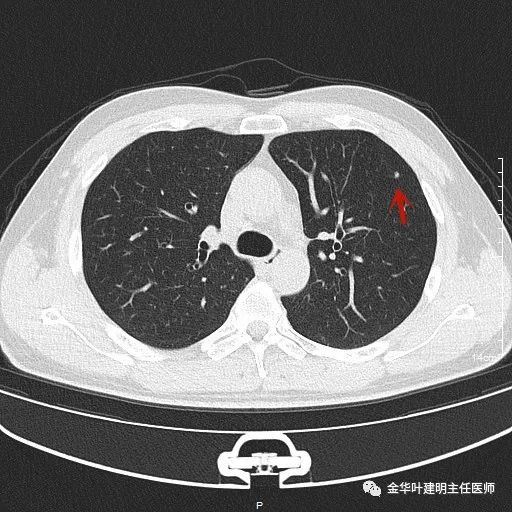

1、以下这种结节是体检发现中最常见的,它们基本上是良性的,可以年度复查:它们都是又上又实的微小结节,直径在5毫米左右或以下。实际上有许多非常焦虑的肺结节病友,他们很多人只是检查发现这种结节。我的建议是:年度复查!若实在不放心,也可半年时复查一次,以确定它不会生长。